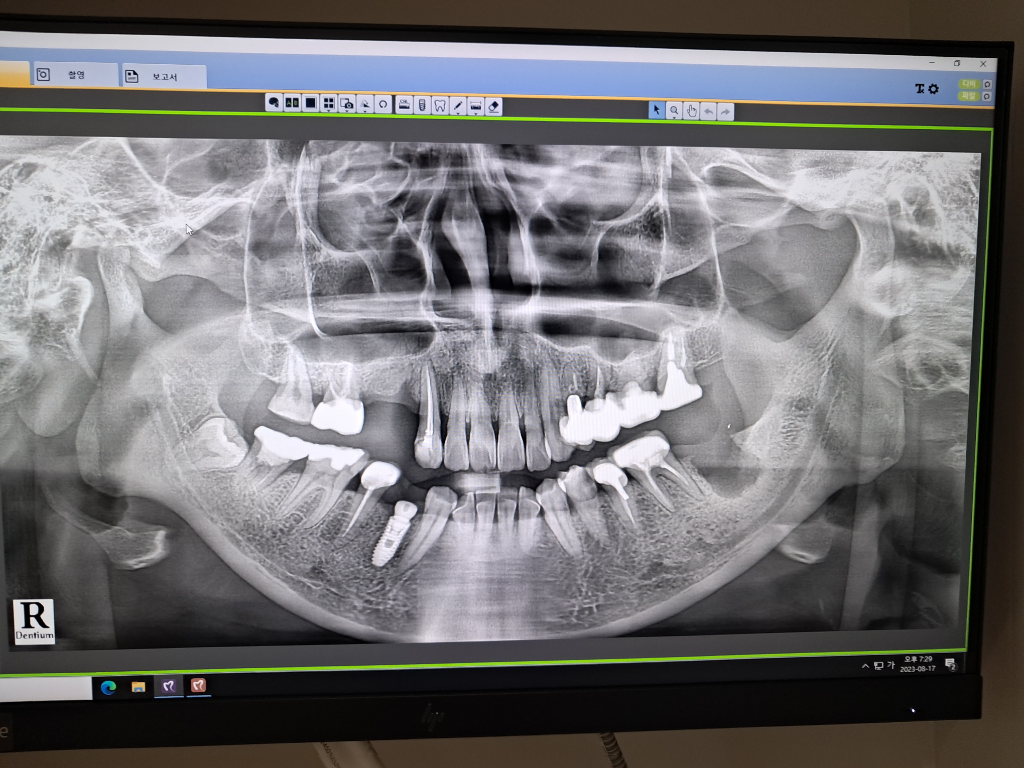

파노라마 사진만 보고 말씀드리는 것이라 정확하지 않을 수 있으니 참고만 하시기 바랍니다.

오른쪽 위 치아의 경우 이제 작은 어금니(4번, 5번)가 2개 다 빠졌고 해당 자리에 2개의 임플란트 식립이 필요합니다. 공간이 타이트하긴 하지만 한개만 심기에는 임플란트 크라운(머리)이 너무 커지고 하중도 많이 가해질 것 같아서 좋지 않습니다. 일단, 2개의 임플란트를 심는다치면 상악동 거상술과 골이식술은 각각 진행되는 것이 아니고 같이 진행됩니다. 상악동 거상술은 위턱의 양쪽에 있는 크기가 큰 공기 주머니의 아래부위 막을 들어올리는 수술입니다. 이걸 하지 않고 그냥 임플란트를 심게 되면 임플란트가 고정이 잘 안될 수도 있고 상악동에 의도치 않게 구멍이 뚫려 버릴 수도 있습니다. 상악동 거상술을 하고 리프팅 하여 생긴 사이 공간에 인공뼈를 넣어둡니다. 그렇게 하여 임플란트 뿌리(픽스처)가 심어질 깊이를 좀 더 확보하는 것입니다. 다만, 이건 정확히 길이를 측정해봐야 알겠지만 짧은 길이의 픽스처를 심는다면 많은 양의 인공뼈는 넣지 않아도 될 것 같습니다.

아래왼쪽의 경우 염증으로 치아가 흔들리거나 깊은 충치로 인해 발치한 지 얼마되지 않은 상태인 것 같습니다. 치과의사의 치료 전략에 따라 발치하고 바로 그 자리에 심는 경우도 있지만 보통은 2~3개월 정도 기다리며 뼈가 차오르고 잇몸이 나은 뒤에 임플란트(픽스처)를 뼈에 박습니다. 아마 염증으로 발치를 했다면 잇몸치료를 먼저 선행적으로 하고 잇몸 상태가 괜찮아지면 그 때 임플란트를 시작할 것 같습니다.